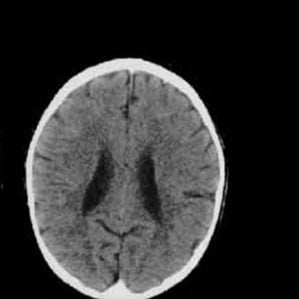

Já essa abaixo é de uma criança da mesma idade, mas que sofreu maus-tratos e que viveu por toda sua vida com uma família abusiva. Dá para perceber que ele é menor e possui algumas partes escuras.

“Estas imagens mostram o impacto negativo que a negligência e os maus-tratos têm no desenvolvimento do cérebro do bebê e criança. Este cérebro da criança que sofreu os maus-tratos é bem menor do que a média esperada para esta idade e tem ventrículos aumentados e atrofia cortical. Essencialmente, isso significa que esse bebê vai sofrer com atrasos no desenvolvimento e problemas de memória”, explicou o professor e psiquiatra Bruce Perry, chefe do setor de psiquiatria do Texas Children’s Hospital, ao Daily Mail.